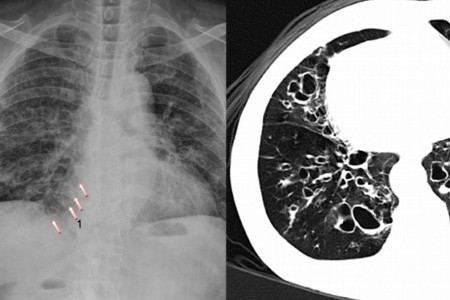

引起支气管扩张的因素很多,生活中我们也应该注意做好防范。大多数患者患上这种疾病都是由肺部感染引起的,比如患者常年呼吸有害气体,导致肺部有害颗粒物堆积,从而使肺部结构遭到破坏,形成支气管扩张,像肺结核、肺癌等疾病也都是由这种原因才形成的。另外身体免疫力差也是患上这种疾病的原因,很多患者由于体质较差,受到感染就会轻易患病。